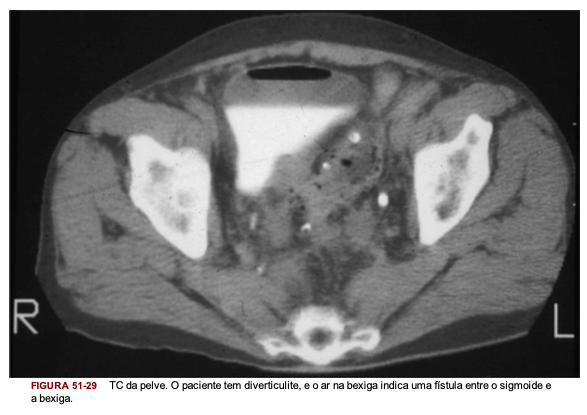

Qual o exame de imagem padrão ouro para o diagnóstico de diverticulite aguda?

O que esse exame fornece?

TC do abdome e pelve: mostra localização, extensão e gravidade da doença; além disso mostra alterações patológicas fora do cólon como um abscesso ou fístula colovesical

TC da pelve mostra diverticulite com abscesso

Evidência da TC de ar dentro de uma bexiga que não foi manipulada previamente